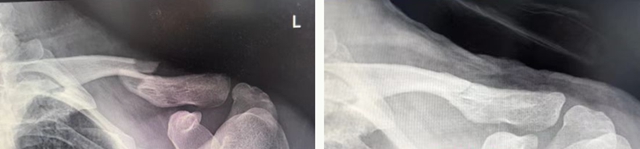

左:复位前 右:复位后

其中,15岁的小林伤势最为严重,骨折为粉碎性,多个骨碎片游离,骨折断端移位明显,并有戳破皮肤趋势。

小林的锁骨骨折最为严重,为粉碎性,若行开放手术,不仅手术切口大,出血多,钢板内固定后还可能影响骨骼后续生长。传统中医手法正骨具有不开刀、不出血、不留疤、费用低等特点。医生运用“推端提按、抱迫靠拢”等正骨手法,蓄力指尖,擒拿扶正,将分散的骨折碎片精准拼接、复位;再用杉树皮小夹板固定,既牢牢锁住骨折端避免再次移位,又不压迫局部皮肤导致皮肤溃疡;同时辅以医院自制的消肿止痛中药外敷,辅以活血化瘀内服方剂,促进骨痂生长和创伤修复。

另外2名少年锁骨骨折轻度移位,病情相对缓和,团队同样采用“手法复位+8字绷带固定”的经典中医方案,快速完成复位固定后,同样施以中药外敷调理,有效缓解疼痛肿胀,促进骨折愈合。